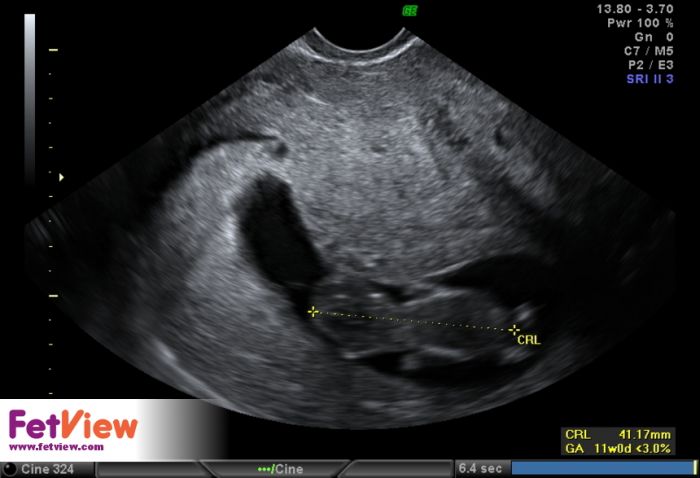

Ahoj holky, tak já byla dneska na kontrole 9+5 a všechno v pořádku, tak se mi šíleně ulevilo. Dostala jsem průkazku a taky se pochlubím fotečkou našeho malého ufounka